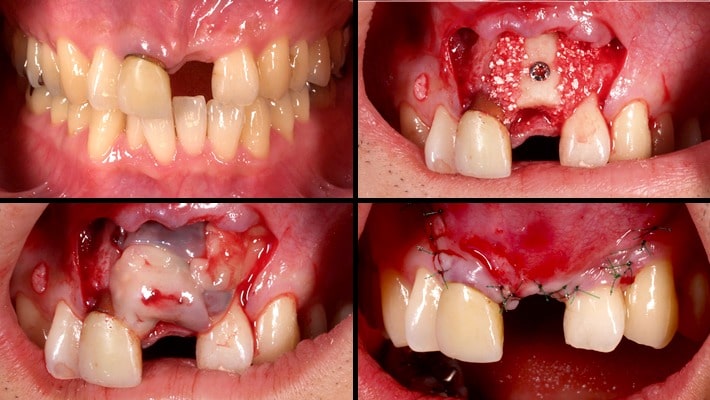

自家骨をブロックで採取して移植(ベニアグラフト)し、骨の厚みを増します。

最善の位置・角度でインプラント埋入